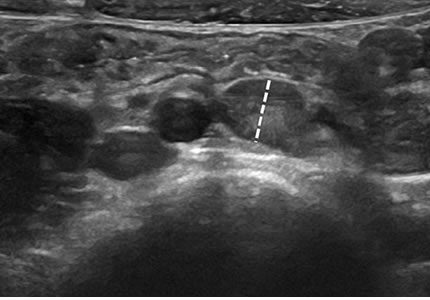

- A comprehensive evaluation of both kidneys to screen for stones, cysts, and structural anomalies. It is an essential investigation for recurrent urinary tract infections (UTIs), "flank" (side) pain, or changes in kidney function.

- £150

- Ideal for: Side pain, recurrent UTIs, and monitoring kidney health.